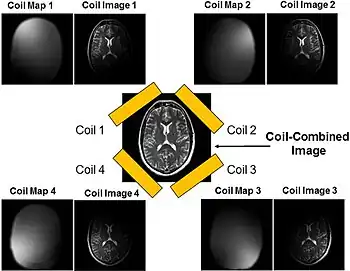

Parallel imaging

Parallel imaging involves the addition of multiple coils surrounding the target with each coil acquiring a fraction of the total image. Because modern GPUs have parallel processing capabilities, they can reconstruct each portion of the image simultaneously. Therefore, the more coils used, the faster the acquisition of the MR images.[16]